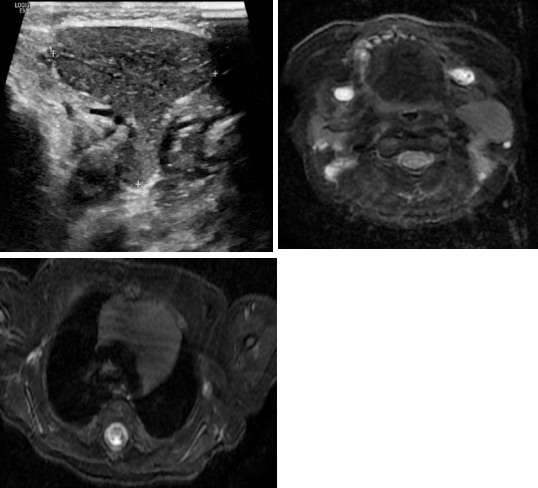

При осмотре: в толще барабанных перепонок пузырьки воздуха, признаков отека или воспаления нет. Аудиография: умеренная кондуктивная тугоухость справа, нормальный слух слева.